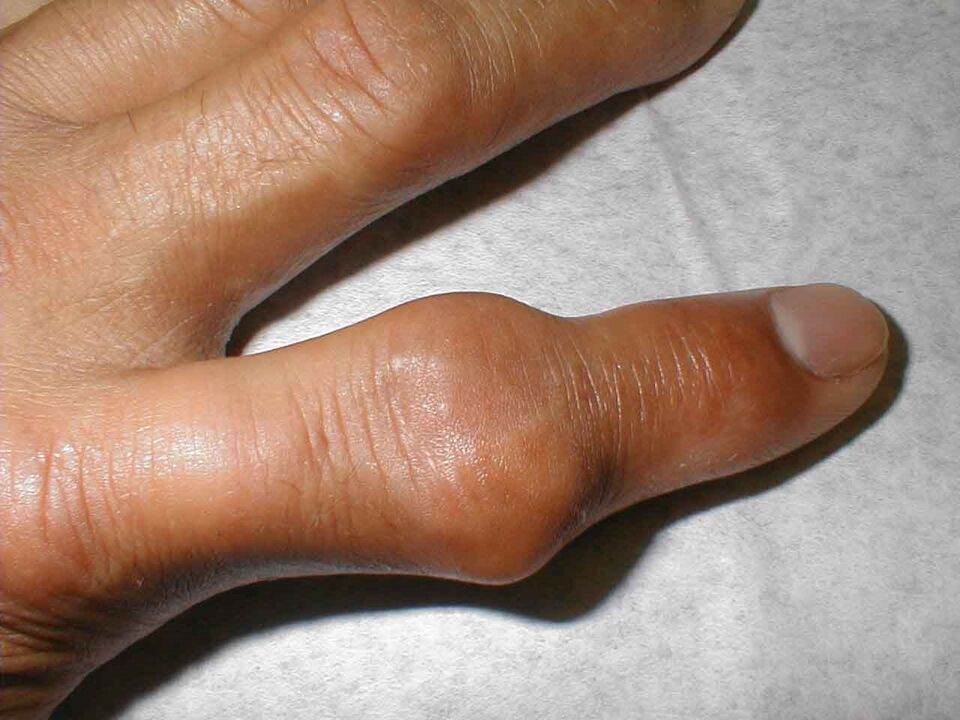

Artrite gottosa

Questa malattia colpisce soprattutto gli uomini, poiché è una conseguenza diretta dei disturbi metabolici. Il corpo produce acido urico in eccesso, i cui cristalli si accumulano nella cavità articolare. Quasi sempre è interessata solo un'articolazione della mano e la malattia progredisce molto rapidamente.

Molto spesso, il paziente si sente assolutamente sano quando va a letto. Ma alle tre o alle quattro del mattino si sveglia con un dolore insopportabile all'articolazione gonfia: questa è un'immagine classica della gotta.

L'articolazione aumenta di dimensioni e diventa rossa. È impossibile toccarlo e gli antidolorifici aiutano poco. Questa grave sindrome dolorosa è causata dall'accumulo di cristalli taglienti di sali (urati) nella cavità articolare, che ad ogni movimento penetrano nei tessuti molli, ferendoli.

Anche dopo aver normalizzato il livello di acido urico nel corpo, l'articolazione appare ancora un po' ingrossata per lungo tempo. Successivamente, è spesso lui a sperimentare nuovamente il prossimo attacco della malattia.